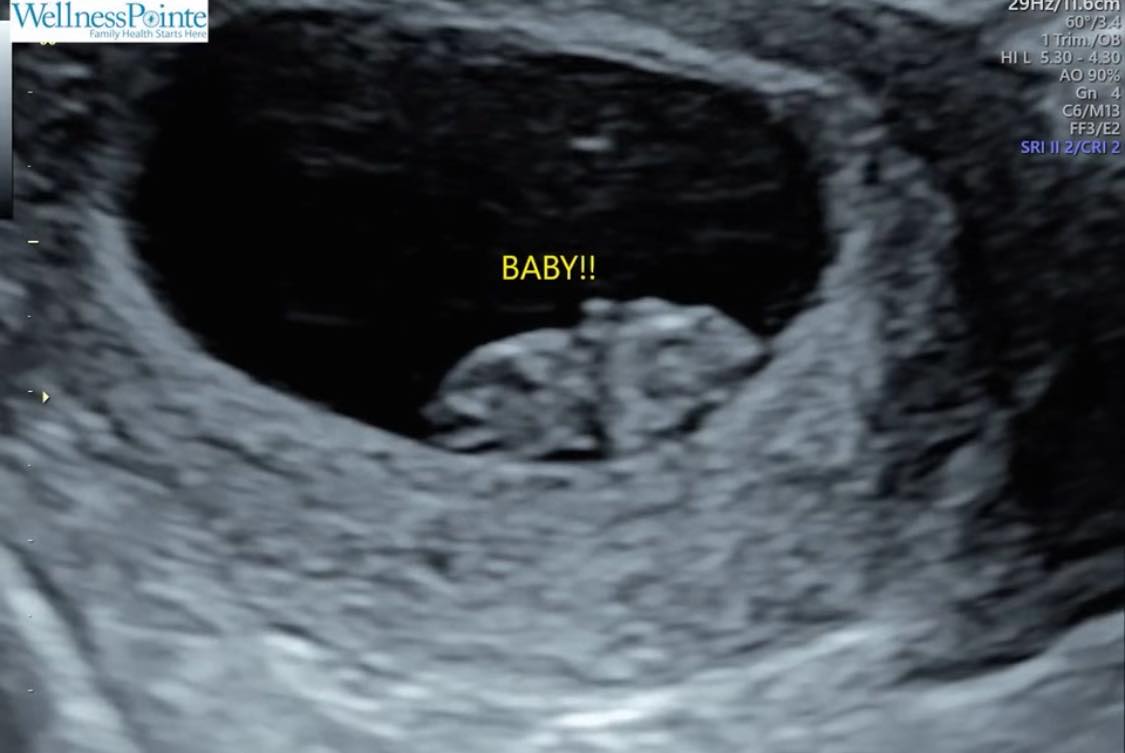

So three months ago we found out we are expecting our second baby sometime in January of 2026, and just yesterday learned we are having another baby girl!